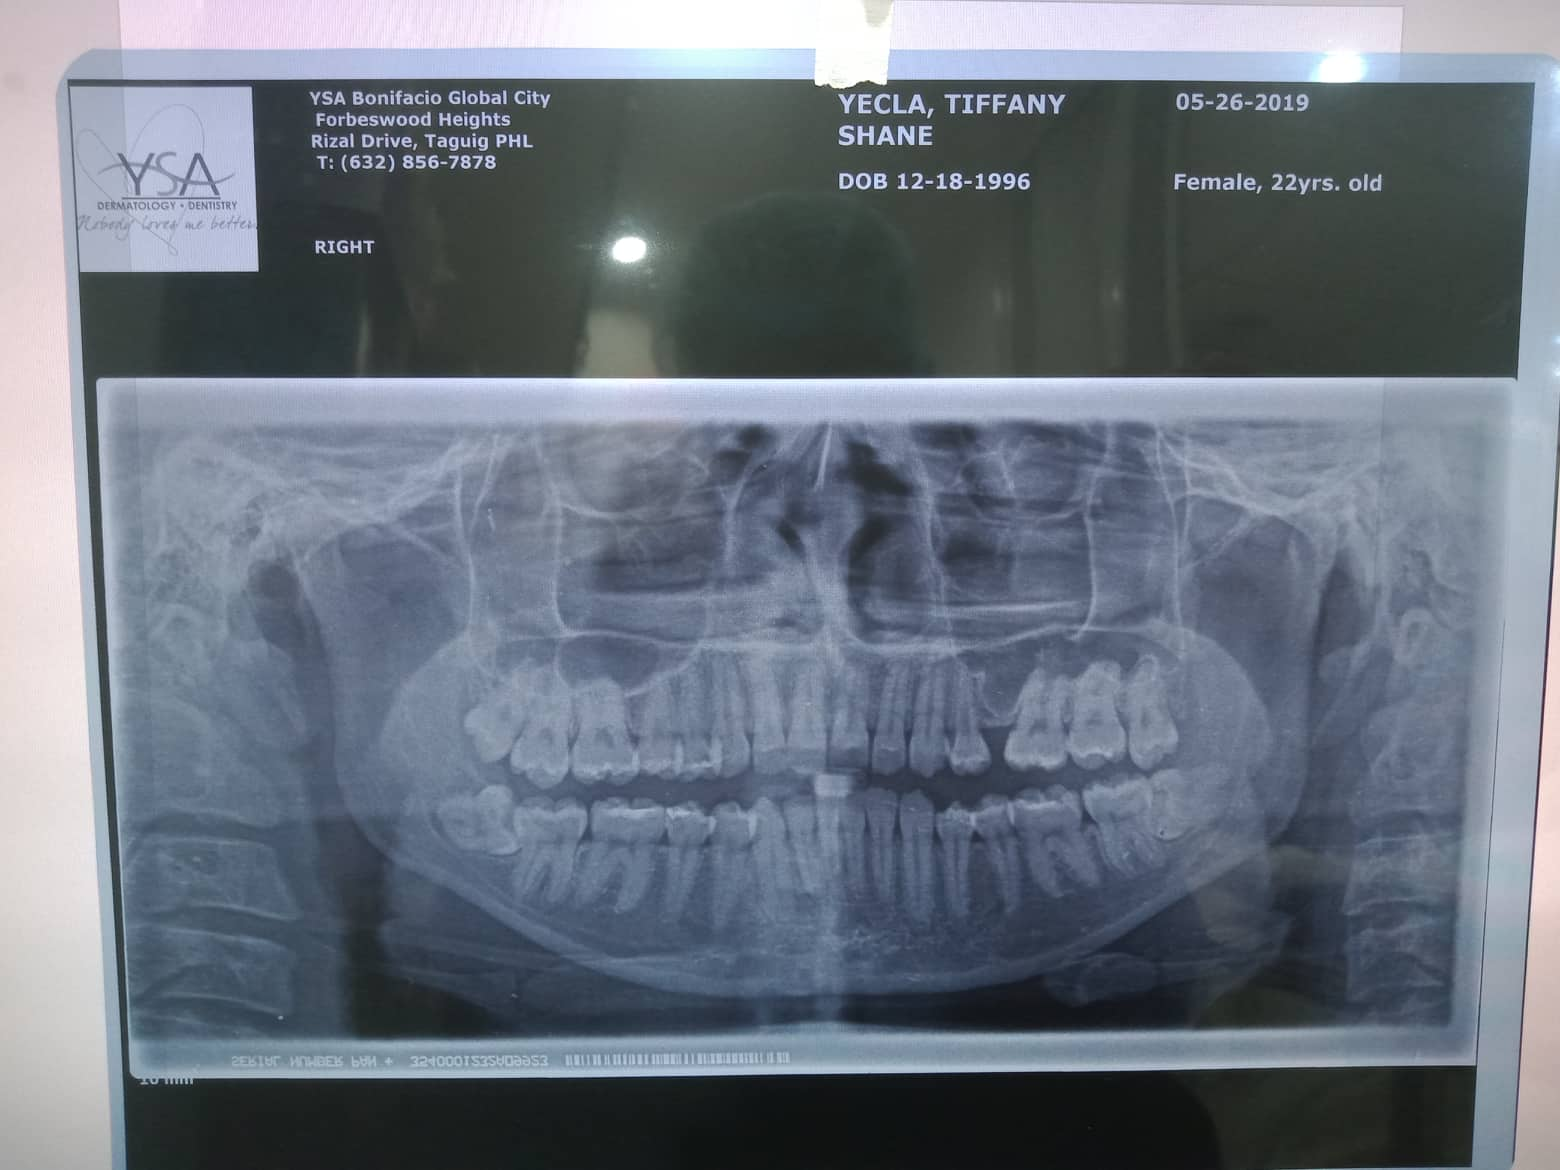

- 08/15/21- adj 16*22UL 18niti 34 09/18/21 - adj. 34^ for removal- for resto 22/34 10/16/21 - REMOVAL OF BRACES RESTO: 17 CAOH occ/14 MO mta/13 LINGUAL DISTAL ESTHETIC 23/22 ALL INCISAL RESHAPING 10/22/21 -lingual retainer up and down wiyh vacuum retainer 3/05/22 LC 14 Mesial + CAOH/ Op 09/08/22 - OP (light) Resto #15 05/13/23- OP(L) For resto #46 06/14/25 OP mild LC #25 fiber, CaoH,ozone,xray 05/21/26 OP